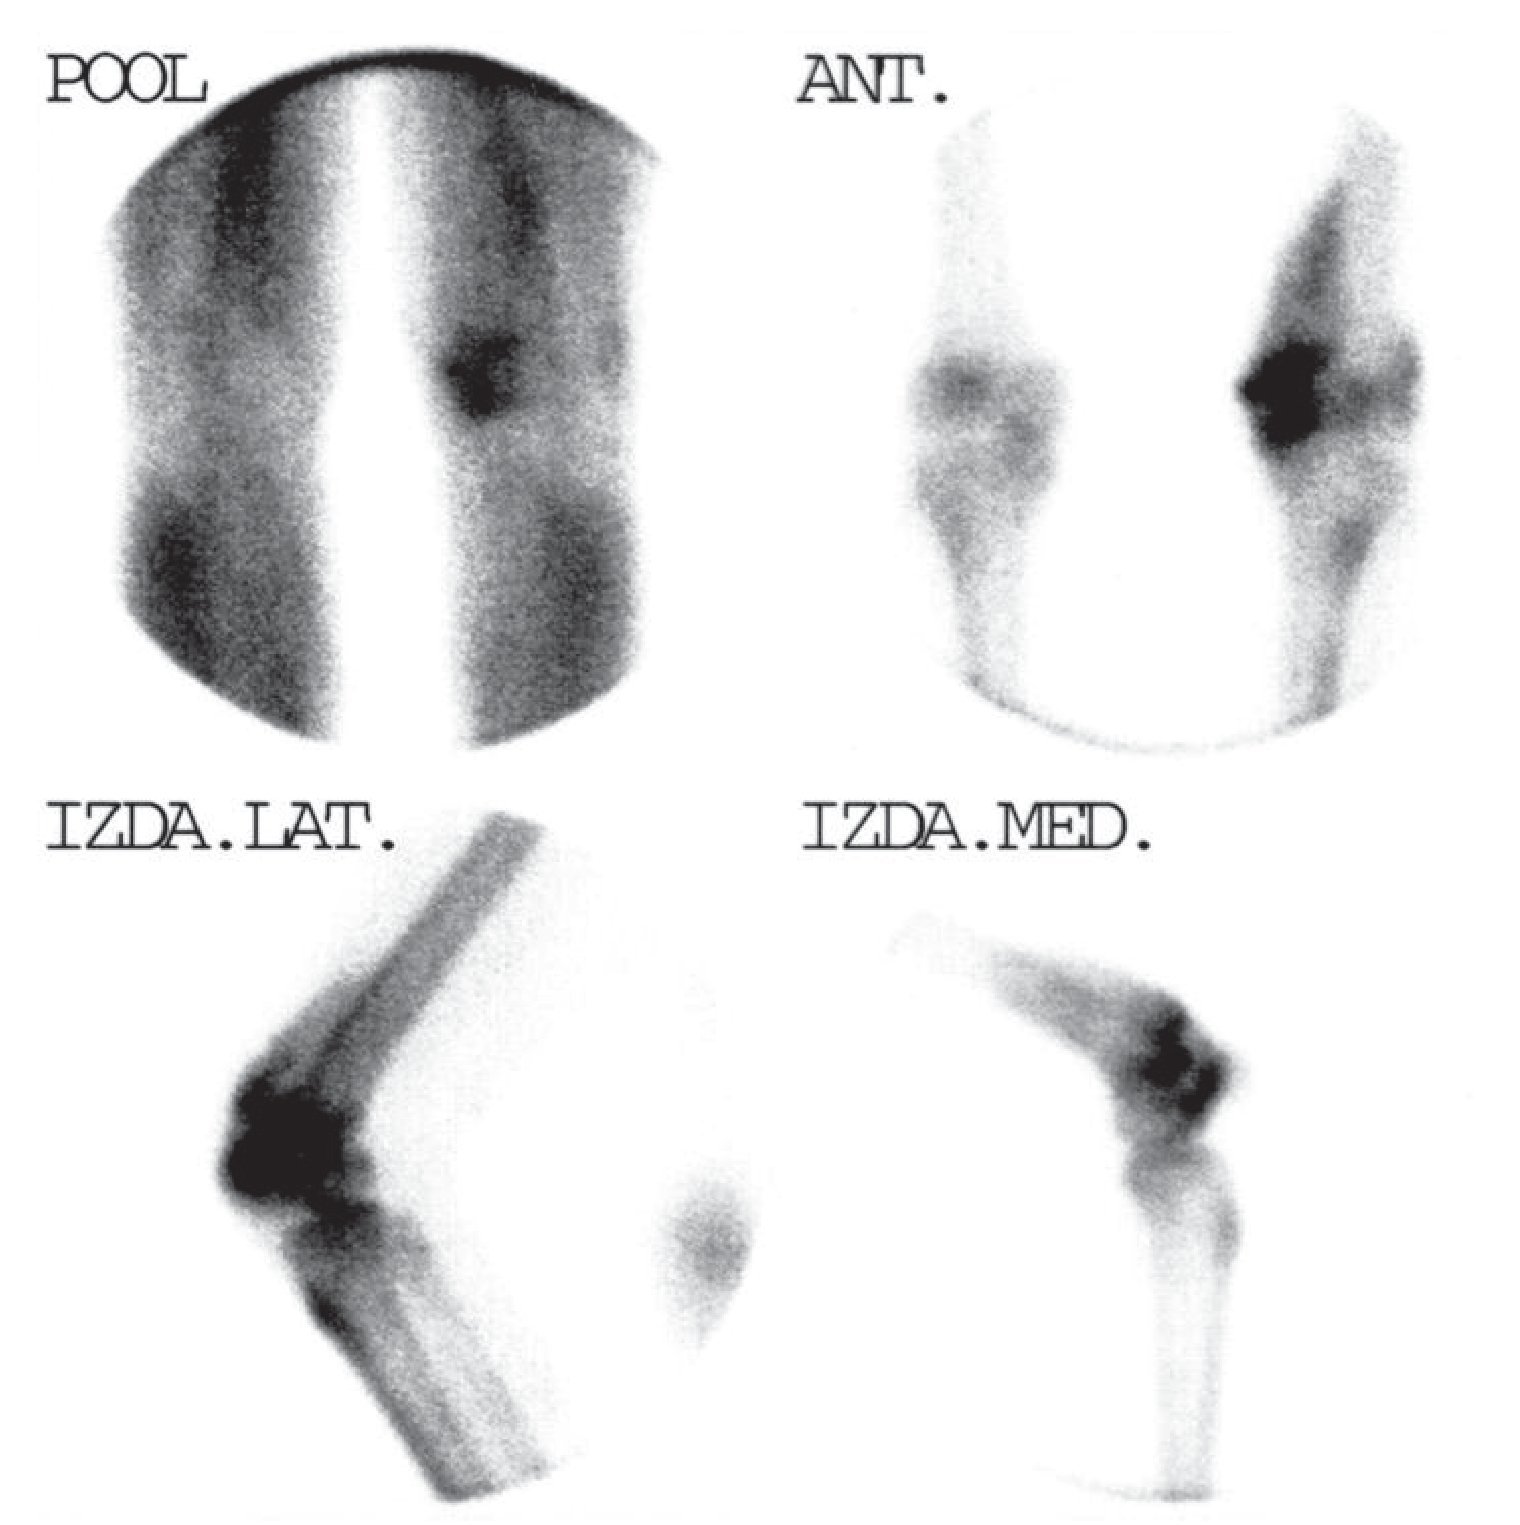

En casos graves, la gammagrafía presenta el patrón de «superscan», con intensa captación difusa de todo el esqueleto, con ausencia de fondo y, generalmente, de las siluetas renales (fig. 3). Al contrario que en el «superscan» de origen metastásico, la captación en cráneo es constante8.

Fig. 3. Gammagrafía ósea con MDP-99mTc de cuerpo completo. Patrón «superscan». Intensa actividad sobre huesos, sin visualizarse las siluetas renales.

La gammagrafía ósea tiene un valor limitado en esta patología y no es útil para su diagnóstico, pero sí para valorar la extensión de la afectación esquelética. Sin embargo, si la gammagrafía ósea es normal, la radiología es también invariablemente normal15. Gammagráficamente, la intensidad de la hipercaptación del trazador en el hiperparatiroidismo primario parece correlacionarse con la gravedad de las alteraciones radiológicas. Existe una amplia variedad de apariencias gammagráficas que van desde la normalidad a un incremento de captación del trazador generalizado, patrón de «superscan», con intensa captación difusa de todo el esqueleto, con ausencia de fondo y, generalmente, de las siluetas renales14. Al contrario que en el «superscan» de origen metastásico, la captación en cráneo es constante. Este patrón gammagráfico se presenta con más frecuencia en el hiperparatiroidismo, especialmente secundario, y en la osteodistrofia renal (ODR), aunque también es posible encontrarlo en exploraciones de pacientes con osteomalacia13.

Es característico hallar en la gammagrafía ósea el típico patrón metabólico, un intenso aumento en la incorporación del trazador, de forma generalizada, en todo el esqueleto, axial y apendicular, y en especial en regiones periarticulares, con distribución de la actividad simétrica y con ausencia o muy débil visualización de las siluetas renales (patrón de «superscan»). Aun cuando la hiperfijación del trazador es difusa, suele hallarse una mayor intensidad de captación a nivel de la calota craneal, mandíbula, esternón, regiones periarticulares, extremos costales y columna vertebral. Así mismo es característico un incremento en la retención corporal total del trazador a las 24 horas y un aumento en la relación entre hueso y tejidos blandos.